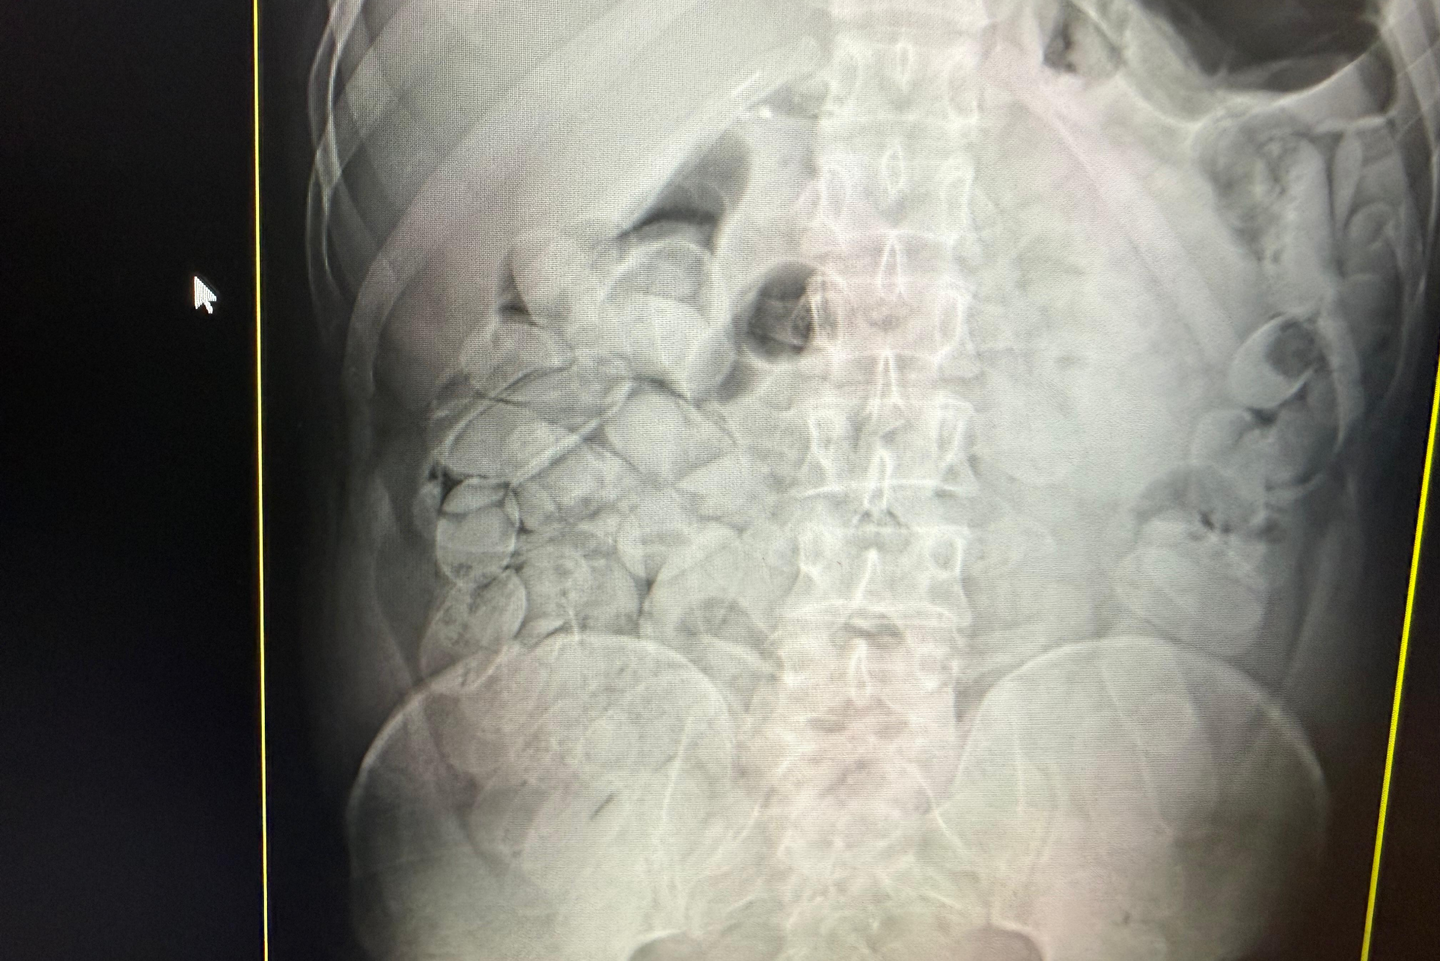

Cães farejadores localizaram drogas em bolsas e caixas de mercadorias. Foto: Divulgação/RFBApós exames foi constatado que 17 pessoas de nacionalidade boliviana haviam ingerido cápsulas de Cocaína, sendo 14 homens e três mulheres.

No total, 18 pessoas de nacionalidade boliviana, foram detidas com aproximadamente 20 kg de pasta base de Cocaína. A apreensão gerou um prejuízo de aproximadamente 1 milhão de reais ao crime organizado. Um dos bolivianos foi encaminhado para a Polícia Federal, e os 17 estão sob custódia no Pronto Socorro Municipal aguardando expelir a droga para em seguida serem encaminhados para a Polícia Judiciária.

17 bolivianos foram identificados com cápsulas de drogas ingeridas. Foto: Divulgação/RFBA Receita Federal destaca seu compromisso no combate aos crimes transfronteiriços por meio de operações integradas com as Forças Armadas, os órgãos de fiscalização e segurança pública, contribuindo para a proteção da economia nacional e o fortalecimento da segurança nas fronteiras brasileiras.